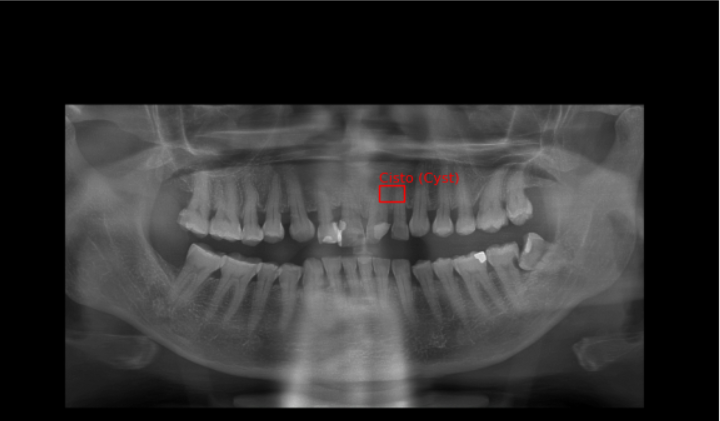

Como mostrado na imagem do dataset acima, temos três pastas chamadas: CREATML (JSON), PascalVOC (XML), YOLO (TXT) com as coordenadas dos cistos, que se mostrarmos utilizando as bibliotecas OpenCV e Matplotlib temos imagens como as ao lado.